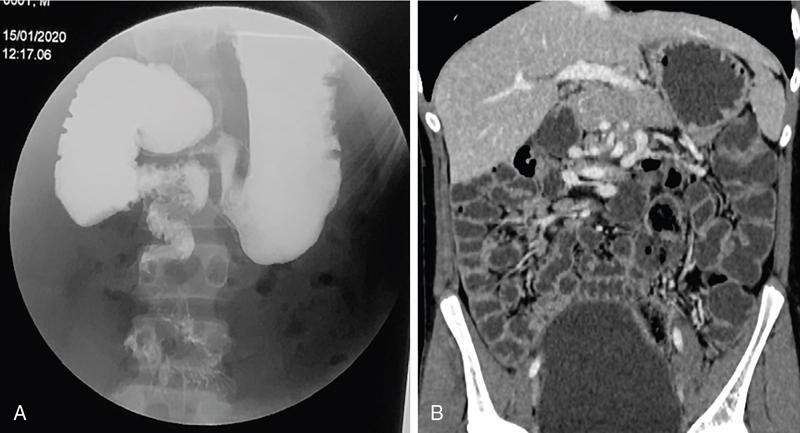

Fluoroscopic barium studies

Computed tomography

CT enterography